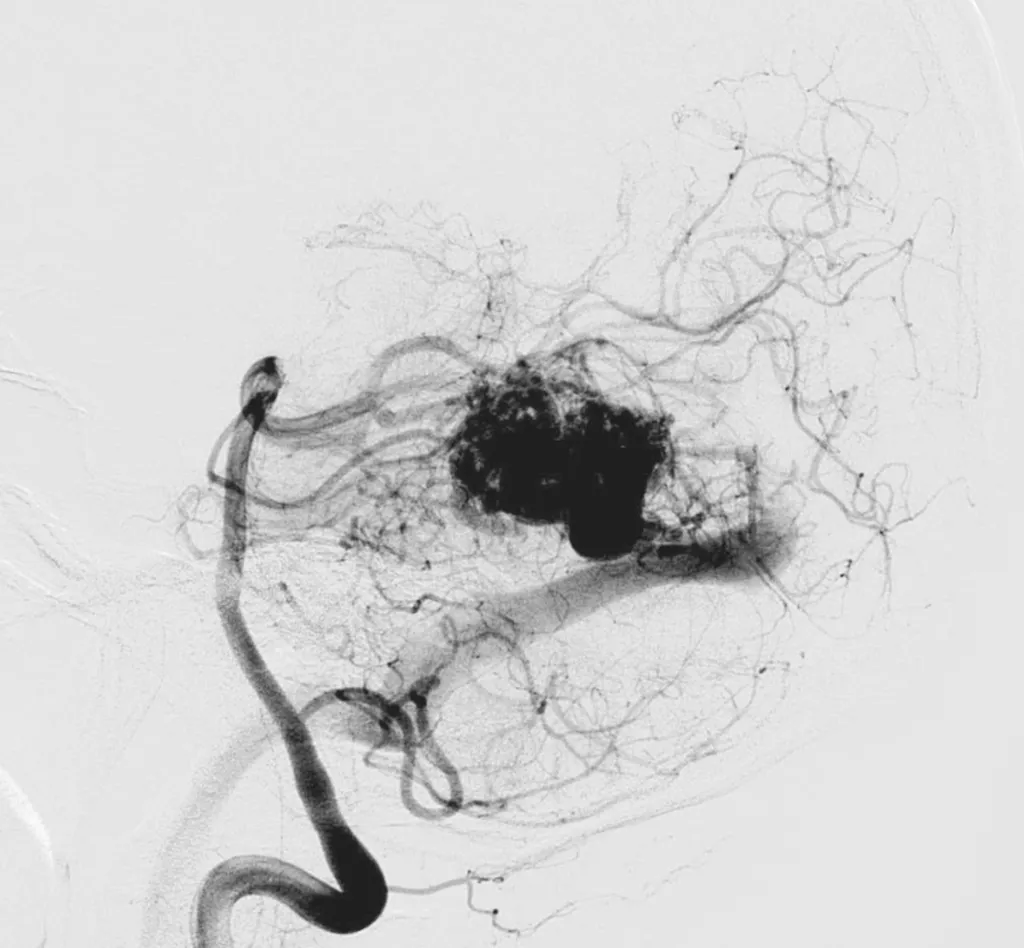

La malformation artérioveineuse (MAV) cérébrale est une anomalie congénitale rare du système vasculaire dans laquelle des artères sont directement connectées à des veines sans passer par le réseau capillaire normal. Ce court-circuit crée une circulation sanguine à haute pression dans les veines, pouvant entraîner une fragilisation progressive des parois vasculaires. Bien que certaines MAV restent silencieuses pendant des années, leur principal risque est la rupture, responsable d’hémorragies intracrâniennes parfois graves.

Le diagnostic repose sur une imagerie cérébrale complète. L’IRM permet de visualiser la malformation et ses éventuelles conséquences sur le tissu cérébral. Le scanner ou l’artériographie cérébrale précisent l’architecture de la MAV, la taille du nidus (zone de connexion anormale) et les artères nourricières. Ces éléments sont essentiels pour planifier le traitement. L’ensemble des dossiers est discuté en réunion de concertation pluridisciplinaire associant neurochirurgiens, neuroradiologues et radiothérapeutes afin d’évaluer les bénéfices et les risques de chaque option thérapeutique.

Le traitement endovasculaire consiste à injecter, via un cathéter, un produit embolisant dans les vaisseaux anormaux pour réduire ou supprimer la circulation sanguine dans la malformation.